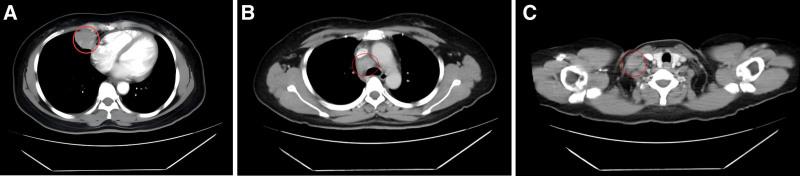

Chest computed tomography revealed a 35 mm × 31 mm mass in the right middle lung with enlarged supraclavicular and mediastinal lymph nodes. A biopsy confirmed the diagnosis of SCC. Staging was determined as cT3N3M1a (stage IVA), and genetic testing revealed no actionable driver mutations, while PD-L1 expression was 30% (tumor proportion score).

The patient initially received first-line treatment with pembrolizumab combined with docetaxel and nedaplatin, achieving partial response. After progression, second-line therapy included gemcitabine and cisplatin chemotherapy with synchronous radiotherapy, followed by camrelizumab and anlotinib. Regular imaging follow-ups guided therapy adjustments, including extended dosing intervals for camrelizumab during disease stabilization.

胸部计算机断层扫描显示右中肺有一个35毫米×31毫米的肿块,锁骨上和纵隔淋巴结肿大。活检确诊为SCC。分期确定为cT3N3M1a(IVA期),基因检测未发现可操作的驱动基因突变,而程序性死亡受体配体1(PD-L1)表达为30%(肿瘤比例评分)。

患者最初接受帕博利珠单抗联合多西他赛和奈达铂的一线治疗,达到部分缓解。进展后,二线治疗包括吉西他滨和顺铂化疗同步放疗,随后是卡瑞利珠单抗和安罗替尼。定期影像学随访指导治疗调整,包括在疾病稳定期间延长卡瑞利珠单抗的给药间隔。